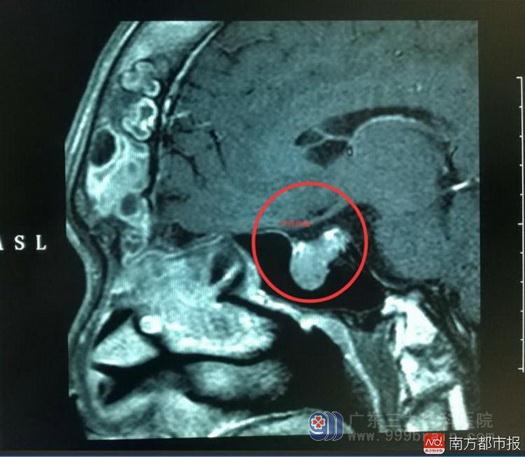

脑垂体位置明显膨大